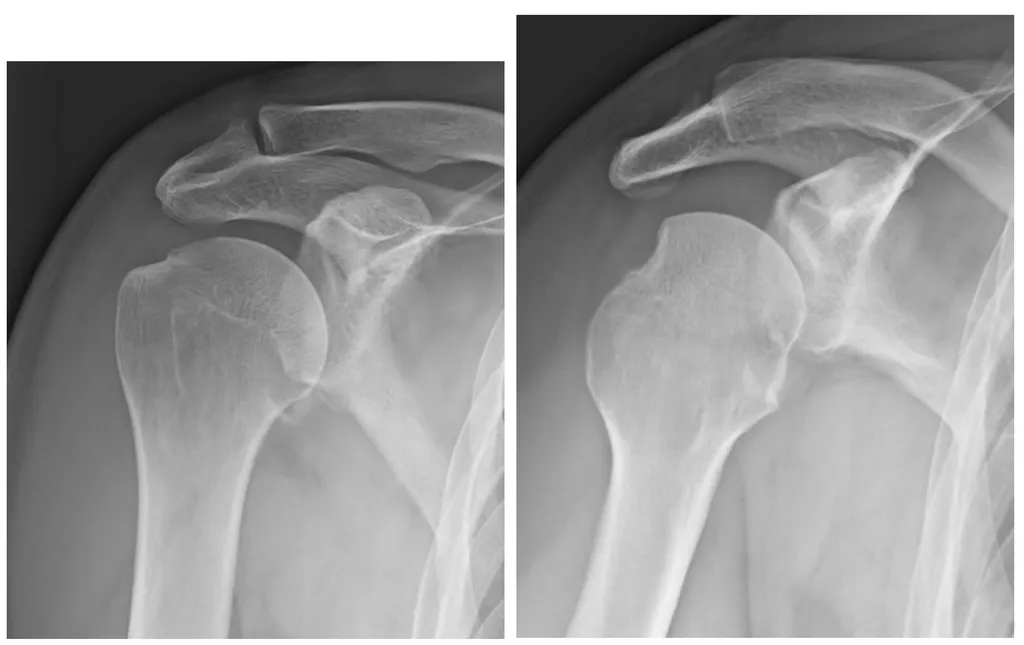

【109-2 醫學(六) 第72題】

47 歲男性主訴受傷後右肩痛,右肩 X 光正位及內旋影像顯示如圖,下列敘述何者錯誤?

這題的解題核心在於仔細辨識肩關節脫臼X光片上常見的骨性病灶,特別是Hill-Sachs病灶和bony Bankart病灶。圖片中可見肱骨頭脫位,且肱骨頭後外側有壓迫性骨折(Hill-Sachs),而肩盂下緣也有輕微骨折(bony Bankart)。